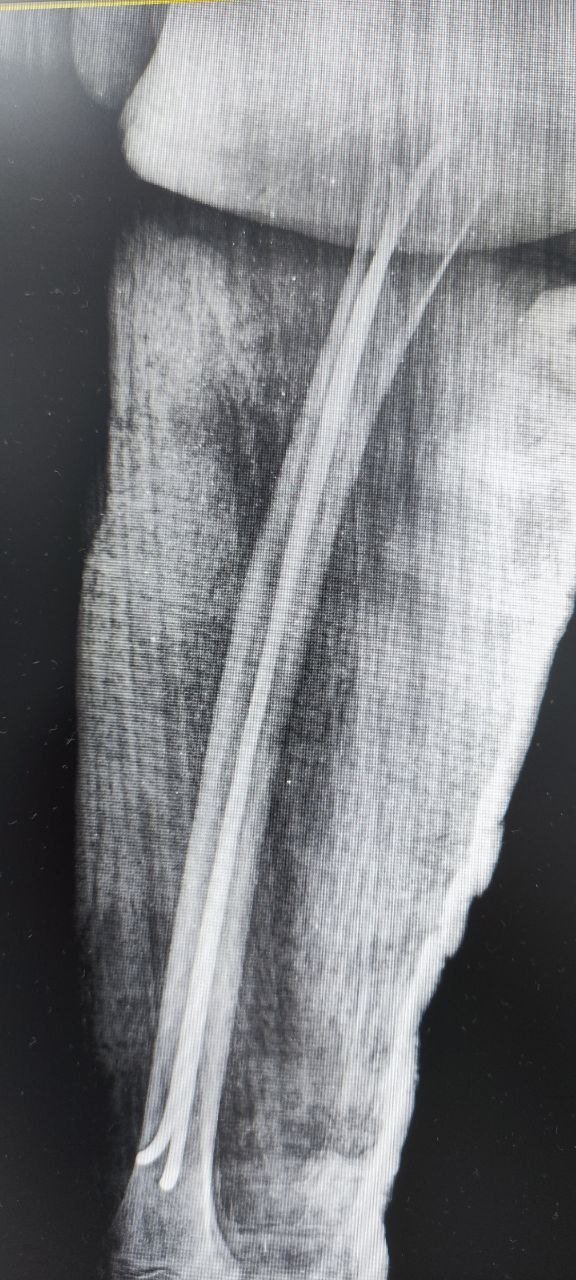

Инцидент произошел накануне. Мальчик попал в приемно-диагностическое отделение ДРКБ и был срочно прооперирован. Сейчас он находится в отделении травматологии и ортопедии, его состояние стабильное.

На сращение перелома уйдет 5–6 недель, а на реабилитацию — несколько месяцев, в зависимости от особенностей организма и соблюдения рекомендаций врачей.